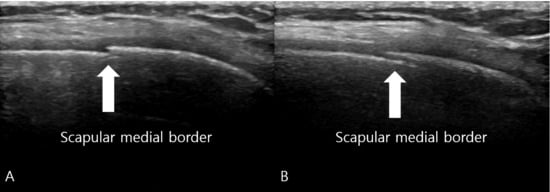

Ultrasonographic Diagnosis and Computed Tomographic Confirmation of a Scapular Body Stress Fracture in an Elite Boxer: A Case Report

Background and Clinical Significance: Scapular stress fractures are exceptionally rare in athletes and are notoriously difficult to diagnose due to their subtle presentation and poor sensitivity on initial radiographs. This case report describes the diagnostic challenge of a scapular body stress fracture in an elite boxer who initially presented with wrist pain. Case Presentation: A 19-year-old right-hand-dominant female elite boxer presented with a three-month history of bilateral wrist pain. Initial examination and MRI were consistent with a triangular fibrocartilage complex (TFCC) injury. Despite conservative management, her symptoms persisted, and she subsequently developed mechanical right shoulder pain and a sensation of instability. Physical examination revealed scapular dyskinesis, with a positive push-up test and weakness on punch protraction. Plain radiographs of the scapula were unremarkable. Point-of-care musculoskeletal ultrasound (MSK US) identified a cortical irregularity at the medial scapular border. A subsequent computed tomography (CT) scan obtained at three-month follow-up definitively confirmed a stress fracture at this site. Treatment focused on scapular stabilization via prolotherapy and activity modification, leading to symptomatic resolution and a successful return to sport. Conclusions: This case underscores the importance of evaluating the entire kinetic chain in athletes presenting with focal complaints. It demonstrates the utility of MSK US as an effective initial screening tool for cortical stress fractures and highlights the necessity of CT for definitive confirmation. Clinicians should maintain a high index of suspicion for scapular stress injuries in overhead athletes with unexplained shoulder dysfunction. Full article

Figure 1